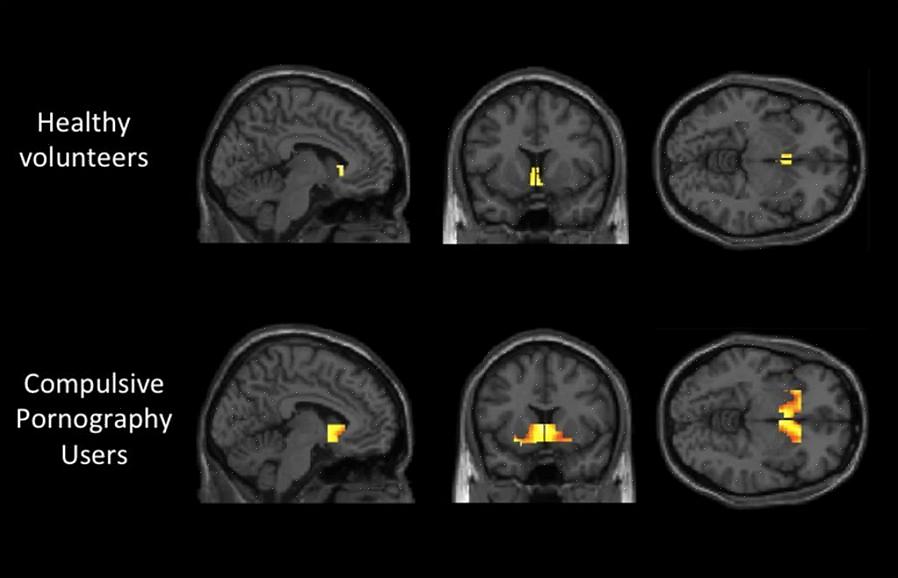

המוח של מכור למין דומה מאוד לזה של מכור לסמים או אלכוהוליסט, אבל למרות שהתמכרות זו לא מחפשת חומר כימי.

האופן שבו מכוונים את החשיבה וההתנהגות שלהם קשורה ישירות להפרעה טורדנית-קומפולסיבית שמובילה אותם למקד את כל מאמציהם בלהשיג יותר גירויים מיניים. הפעילות המוחית של התמכרות למין משקפת את אותה פעילות כמו התמכרות לסמים.

ד"ר ולרי מון, כחלק מצוות המחקר של המחלקה לפסיכיאטריה באוניברסיטת קיימברידג', אומרת שהם עדיין לא יכולים לדבר על התמכרות למרות מחקר שנערך על 19 גברים בוגרים שגילה שיש פעילות מוחית מוגברת בשלושה אזורים ספציפיים של המוח החופף להתמכרות לסמים ולאלכוהול.

המוליך העצבי הדומיננטי של מכור למין הוא דופמין אשר קשור למוטיבציה ומשוב מתגמולים. מחקרים אחרונים אחרים מראים שיש הבדלים בין המוח של אלכוהוליסט לאדם שנהנה לשתות אלכוהול מבלי לסבול מתלות כלשהי.